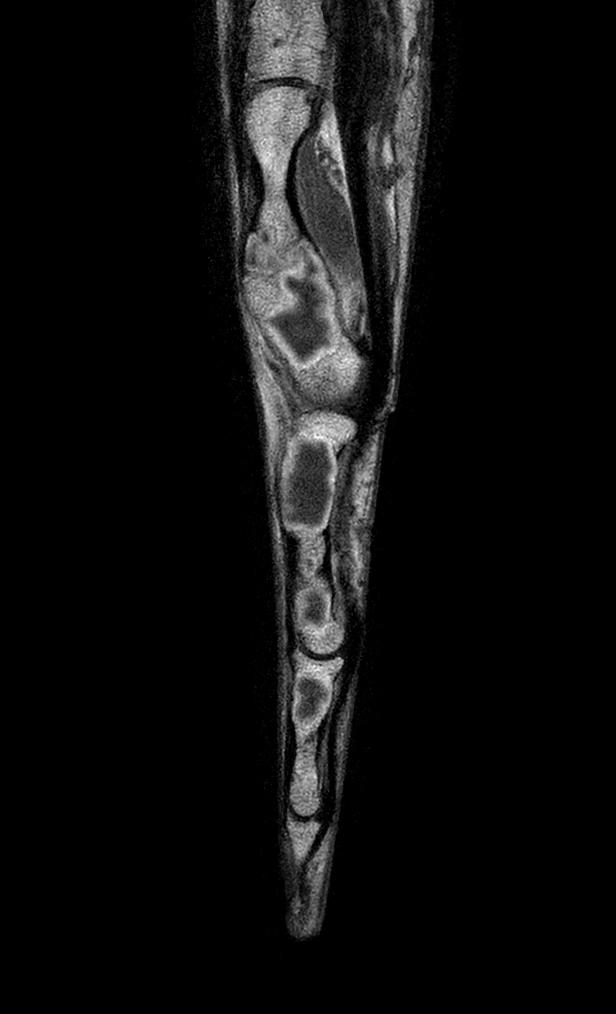

Coronal T1w mDIXON XD TSE (Water only)

Coronal T1w mDIXON XD TSE (In Phase)

Coronal T1w mDIXON XD TSE (Partial FatSat)